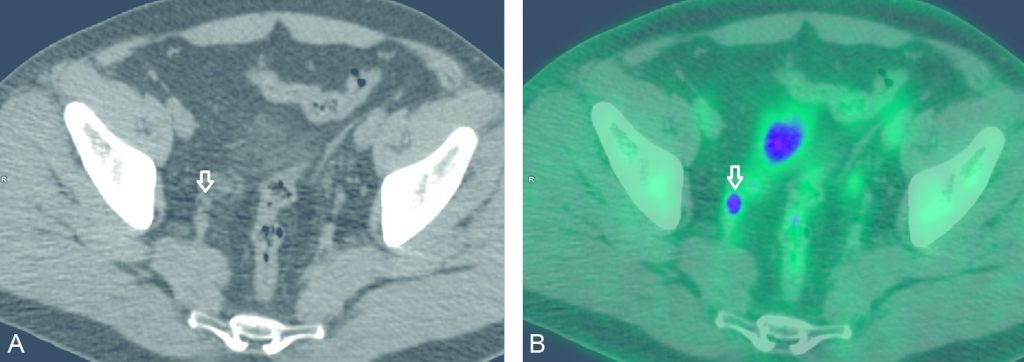

Le critère diagnostique d’adénopathie métastatique pelvienne est identique en TDM et en IRM et fondé uniquement sur la taille (8 mm de plus petit axe dans le plan axial). Il s’agit d’une masse supplémentaire autour des pédicules vasculaires pelviens. La sensibilité globale de ces deux examens est médiocre. La TEP-TDM au 18FDG recherchera un foyer d’hypermétabolisme (figure 33.4).

Fig. 33.4 Images TEP au 18FDG réalisées pour bilan d’extension initial d’un cancer urothélial de vessie infiltrant le muscle.

Les images en coupe axiale TDM (A) et TEP-TDM (B) mettent en évidence un hypermétabolisme suspect d’une extension lymphatique iliaque externe droite (flèche), confirmée par le curage lymphatique

Source : CERF, CNEBMN, 2022.